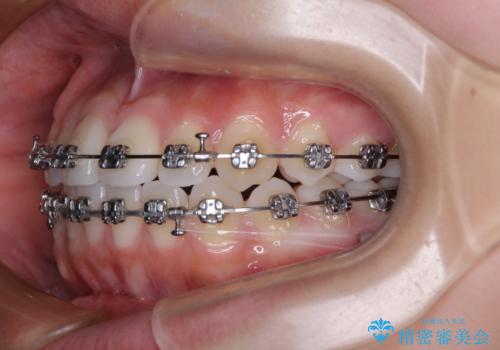

前歯のデコボコを楽して改善 ワイヤー装置による矯正治療

- メタルブラケット

- 前歯のデコボコを治したいとのことで来院された患者様です。

インビザラインによるマウスピース矯正も適用となる歯列でしたが、できる限り楽して、短期間で治したいとのことで、ワイヤー装置にて矯正治療を行うこととしました。